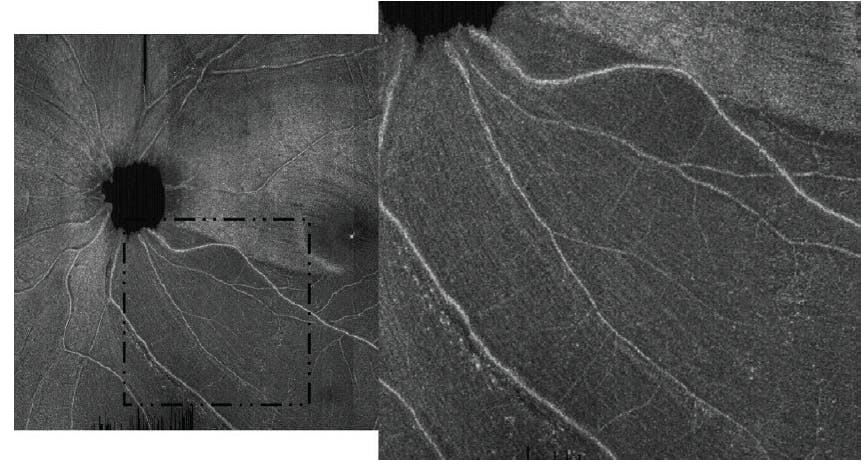

The image quality of ROTA—like conventional OCT scans—can be compromised in eyes with dense media opacities, a low signal-to-noise ratio, or motion artifacts. As with red-free RNFL photography, the detection of RNFL defects using ROTA is largely subjective, but it is feasible to measure the area and the angular width of RNFL defects. We found that the interobserver agreement for the detection of RNFL defects among glaucoma specialists and residents was high; the test-retest variability of ROTA assessment was low; and, more importantly, the ROTA-based assessment of RNFL defects outperformed OCT RNFL/GCIPL thickness analysis with RNFL/GCIPL defects defined with reference to the normative distribution of RNFL/GCIPL thickness.6 With high-density raster scans, ROTA can detect fine details of axonal fiber bundles (Figure 4). ROTA can also play an important role in determining the involvement of the papillomacular and papillofoveal bundles in early glaucoma7 and identifying different patterns of RNFL defects in nonglaucomatous optic neuropathies.6 We are currently working with several members of industry to deploy ROTA in clinical care, and we hope that the paradigm facilitates the early detection of glaucoma to avert its progression.

Figure 4. A high-density raster ROTA scan (28º x 30º with 1536 x 729 pixels) shows residual axonal fiber bundles over an inferotemporal RNFL defect. Adapted with permission from Leung et al.6